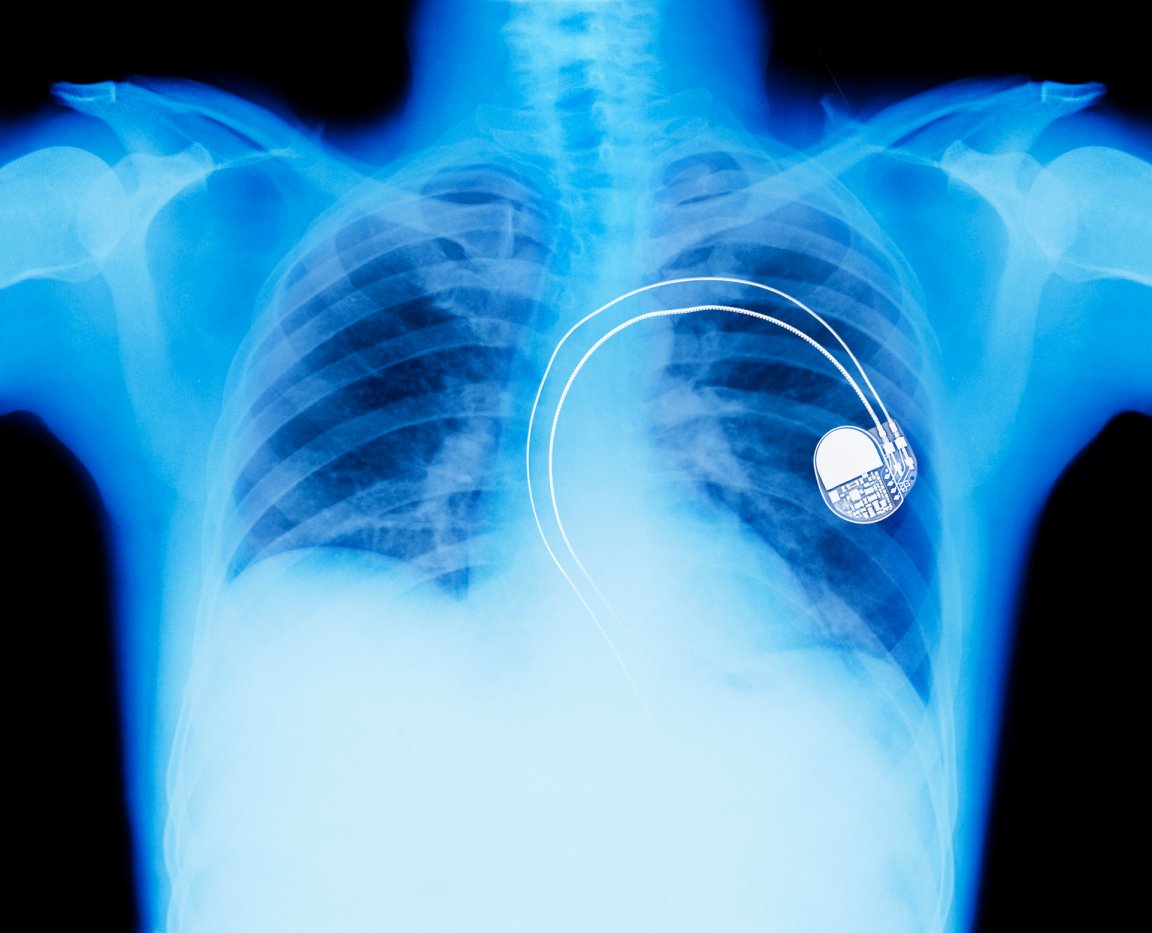

Dr. Geetha Srinivasan, the research leader at Queen’s University’s Ionic Liquid Laboratories (QUILL) research centre, explained to the BBC how the flexible supercapacitor could power medical devices, “In medical devices such as pacemakers and defibrillators there are two implants, one which is fitted in the heart and another which holds the metal based, rigid batteries—this is implanted under the skin,” Dr. Srinivasan said. “The implant under the skin is wired to the device and can cause patients discomfort as it is rubs against the skin. For this reason batteries need to be compatible to the human body and ideally we would like them to be flexible so that they can adapt to body shapes.”